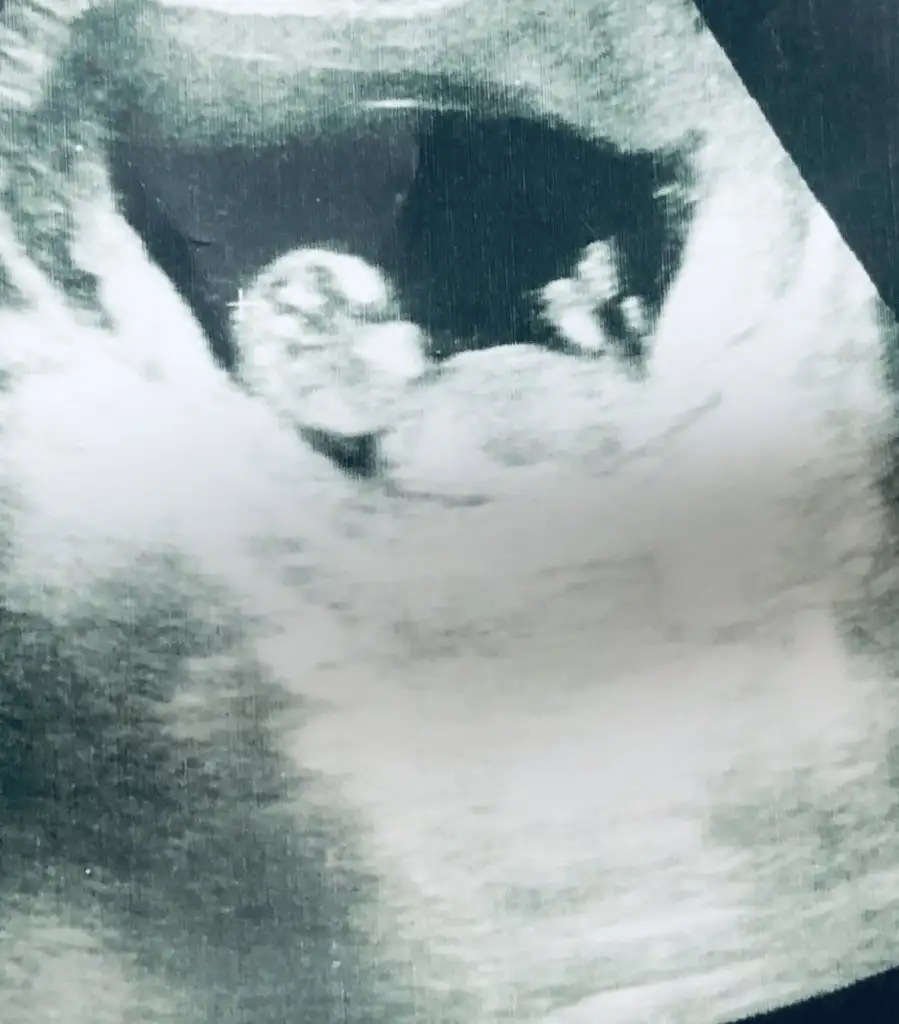

Kaç haftalık erkek gibibanada yardimci olursaniz cok sevinirm yorumlarinizi bekliyrum lutfen

11 yada 12 hafta olmalı nub için kafa şekli erkek gibi ama tutmayabilir siz 11 yada 12 hafta usg paylaşınmerhaba dün 2 farklı yerde ultrason çektirdik ama cinsiyetini öneremedik rica etsem usg bakıp tahmininizi söyliyebilirmisiniz 16. haftayıda geçtik hayırlısıyla teşekkkürler.Eki Görüntüle 2309422

bu 12 haftalıkken

Selam hanımlar benimki de 12 haftalık sizce cinsiyeti neKız gibi net degil usg kız gibi diyorum